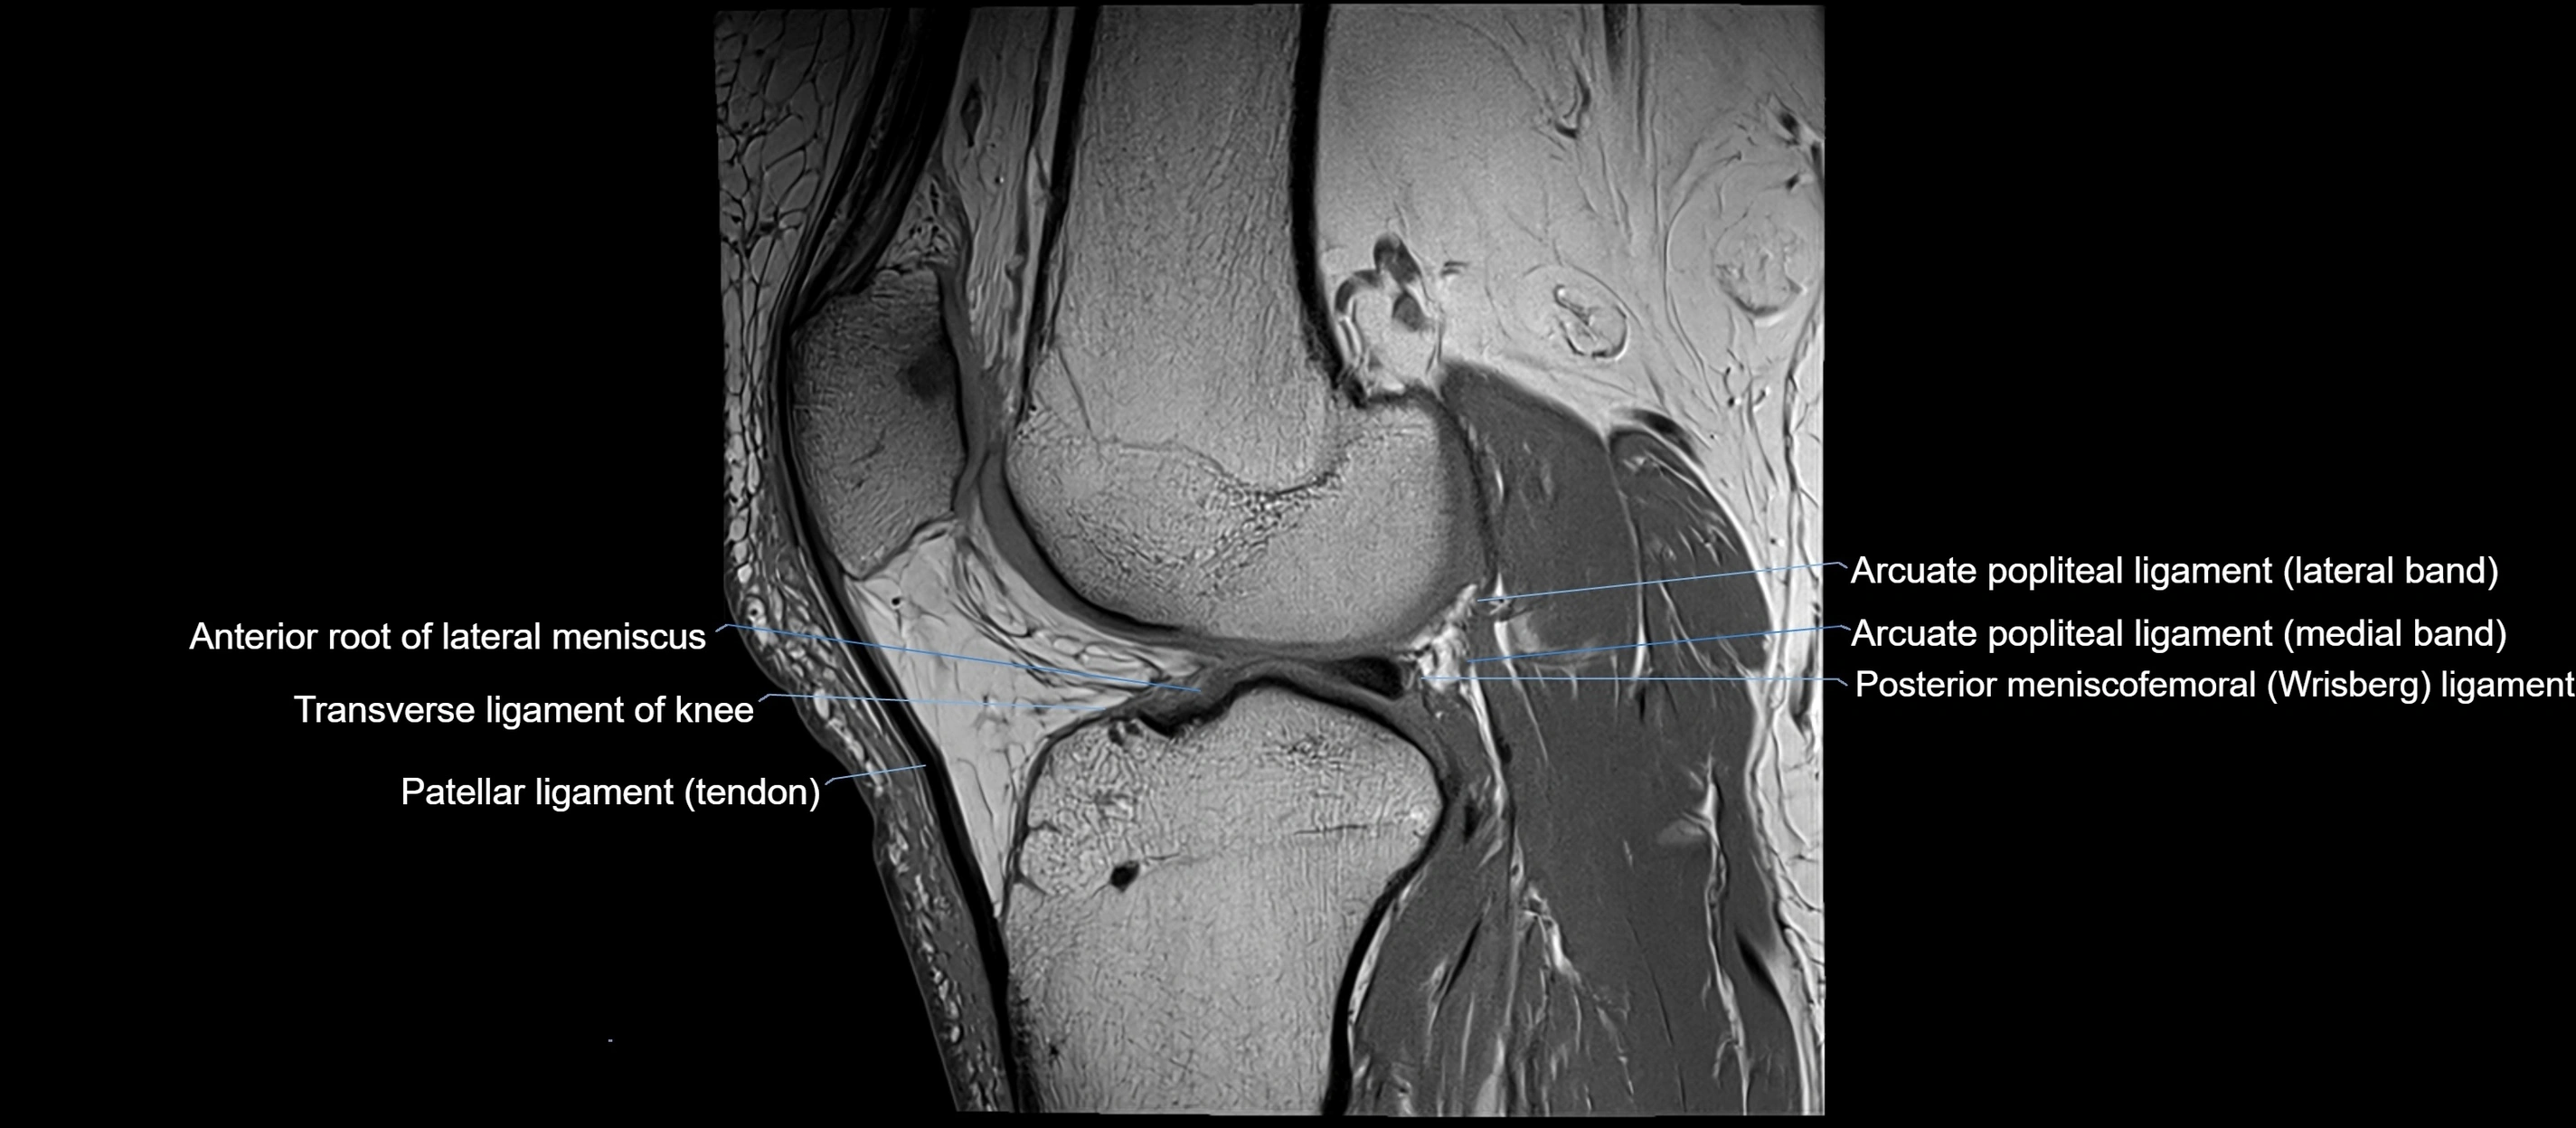

MRI images

image